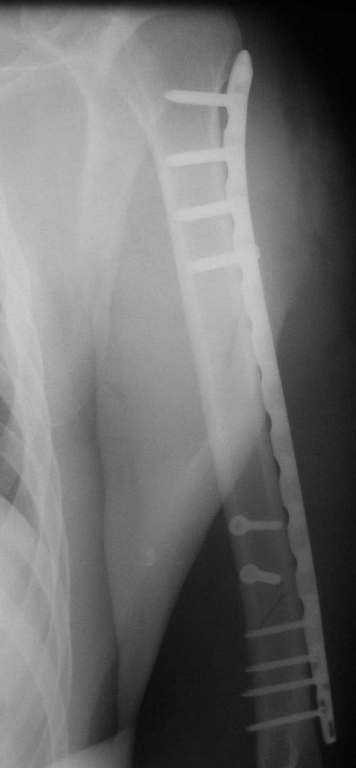

Красиво и быстро?! - две пластины + 18 шурупов.

Идеальная репозиция?! -На снимочке A-P проeкции видна "зазубрина" по суставной поверхности, латеральный снимок - тоже не идеально.

Множество мелких FB в кости.